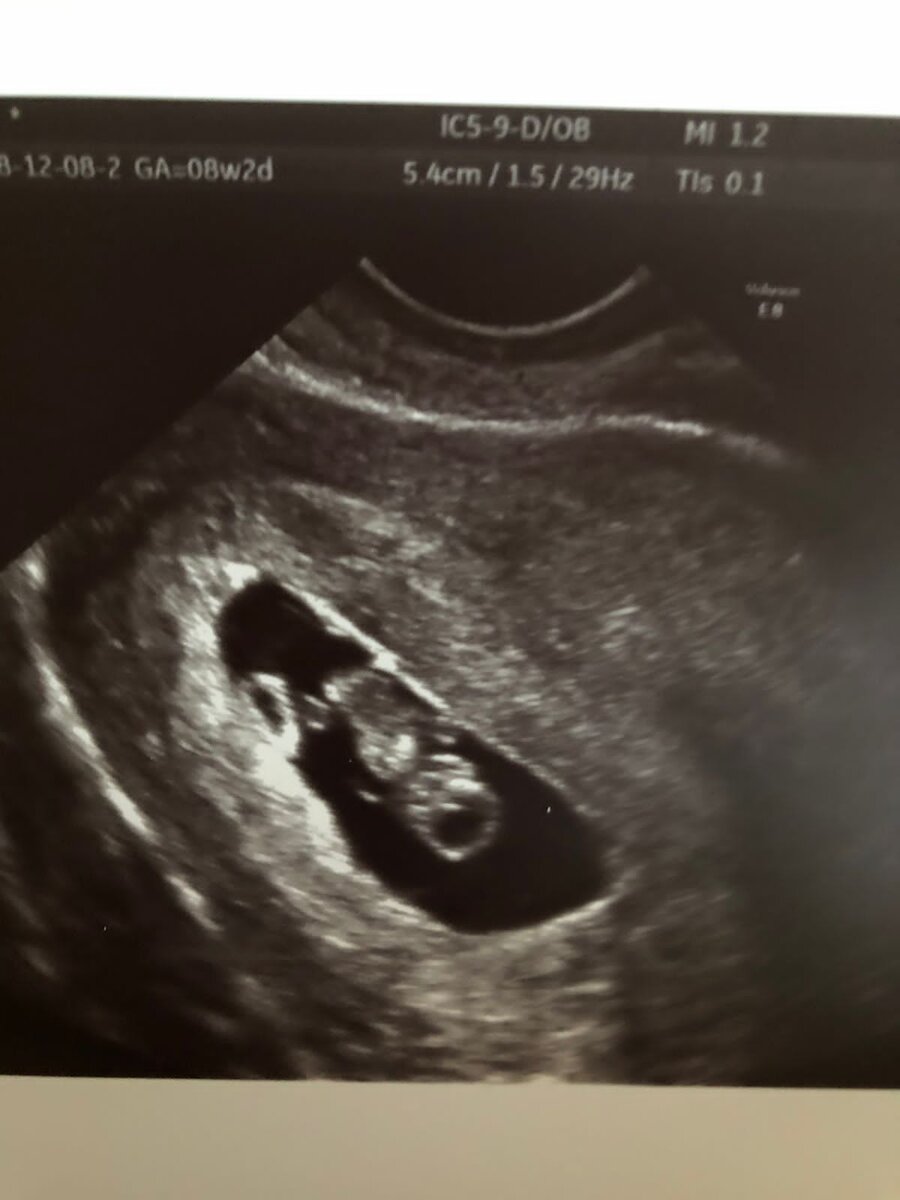

Сегодня мне бы хотелось рассказать как тяжело нам дался наш ангелок, наш сынок, наша гордость! У нас по женскому роду, есть наследственная Эклампсия.  Откуда я узнала об этом, у меня моя родная сестра родила полностью здорового ребёнка, но во время родов у неё упало давление и началась эклампсия с последующим диагнозом HELLP-синдром — редкое тяжёлое осложнение в акушерстве, возникающее, как правило, в III триместре беременности, чаще на сроке 35 или более недель. В 31 % случаев заболевание может возникать в первую неделю после родов.  У моей сестры была самая тяжёлая форма, у неё отказали все органы кроме сердца. Это было тяжело безумно, но мы справились, сестру выходить и все хорошо.  Ну чтож вернёмся к нашей истории.  Когда узнали что я беременна, мы были рады, но и конечно был ком в горле.  Мама с папой были рады и одновременно напуганы ведь, они чуть не потеряли свою дочку.  Беременность проходила нормально, но меня жутко доставали постоянные анализы в двух больницах. Пришёл тот м

Пришёл тот момент и срок беременности когда мне можно было сдавать на наследственные заболевания.